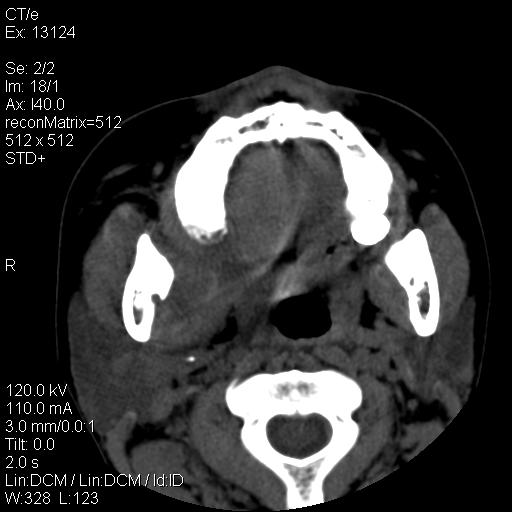

女,29岁,右下磨牙痛,因产后2月,故未治疗。现右颌肿痛伴张口困难。请大家看看右侧鼻咽部、口咽部是否

1.考虑右侧下颌区脓肿(牙源性)

考虑右下智齿冠周炎伴周围软组织炎症,脓肿形成

1)考虑右侧下颌区软组织脓肿(牙源性)。2)鼻咽部炎性改变;建议追踪复查。3)右侧上颌窦炎。4)双侧下鼻甲黏膜肥厚。

1)考虑右侧下颌区牙源性软组织脓肿。2)右侧上颌窦炎。3)双侧下鼻甲黏膜肥厚。4)鼻咽部炎性改变;建议追踪复查。

考虑右下智齿冠周炎伴周围软组织脓肿形成。